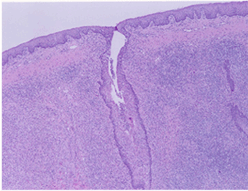

주요임상증상